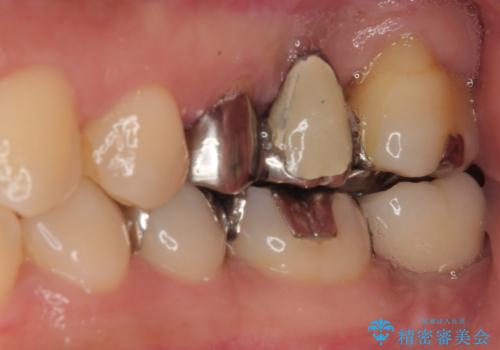

- 奥歯を抜歯してから放置しているとのことで来院された患者様です。

歯が割れて抜歯になってしまったとのことで、咬合力に抵抗できるよう、インプラントによる補綴治療を行うこととしました。